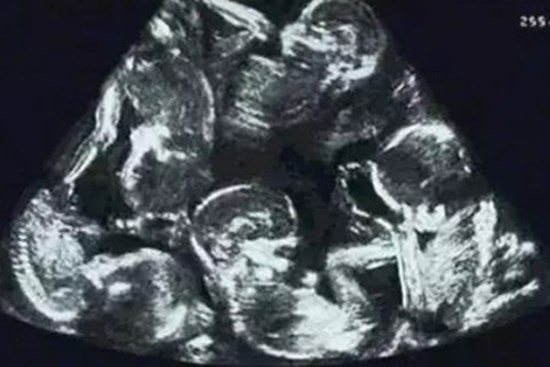

Những ca sinh 3-4-5 đặc biệt nhất Việt Nam, thế giới cũng hiếm có khó tìm

Một số trường hợp đa thai hy hữu khác, những “huynh đệ sum vầy” từ trong bụng mẹ được truyền thông và cộng đồng chú ý.